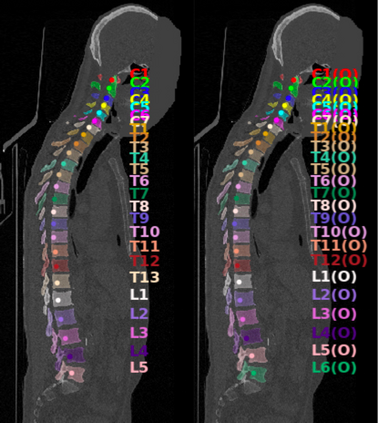

Vertebrae localization, segmentation and identification in CT images is key to numerous clinical applications. While deep learning strategies have brought to this field significant improvements over recent years, transitional and pathological vertebrae are still plaguing most existing approaches as a consequence of their poor representation in training datasets. Alternatively, proposed non-learning based methods take benefit of prior knowledge to handle such particular cases. In this work we propose to combine both strategies. To this purpose we introduce an iterative cycle in which individual vertebrae are recursively localized, segmented and identified using deep-networks, while anatomic consistency is enforced using statistical priors. In this strategy, the transitional vertebrae identification is handled by encoding their configurations in a graphical model that aggregates local deep-network predictions into an anatomically consistent final result. Our approach achieves state-of-the-art results on the VerSe20 challenge benchmark, and outperforms all methods on transitional vertebrae as well as the generalization to the VerSe19 challenge benchmark. Furthermore, our method can detect and report inconsistent spine regions that do not satisfy the anatomic consistency priors. Our code and model are openly available for research purposes.